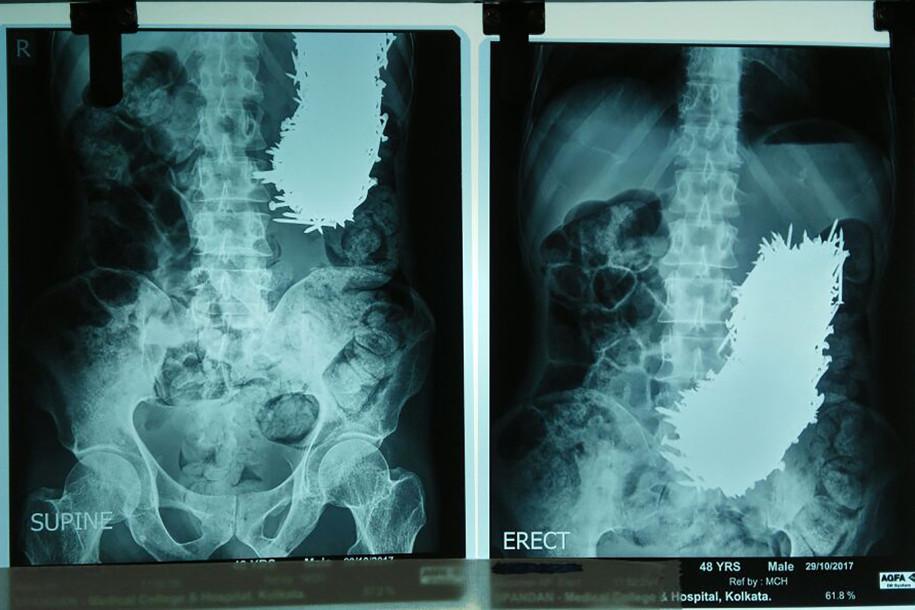

Sau khi chụp CT, các bác sĩ đều bị choáng khi trong bụng nam bệnh nhân có tới 600 chiếc đinh. Tuần trước, họ đã tiến hành phẫu thuật lấy các dị vật ra khỏi dạ dày của Dhali.

Các bác sĩ phát hiện ra có dị vật trong bụng ông Dhali sau khi chụp CT

Đội ngũ y bác sĩ đã phải dùng nam châm để hút 600 chiếc đinh trong dạ dày bệnh nhân